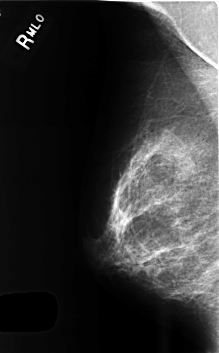

C_0503_1.RIGHT_MLO

RIGHT_MLO LINES 4584 PIXELS_PER_LINE 2840 BITS_PER_PIXEL 12 RESOLUTION 50 NON_OVERLAY